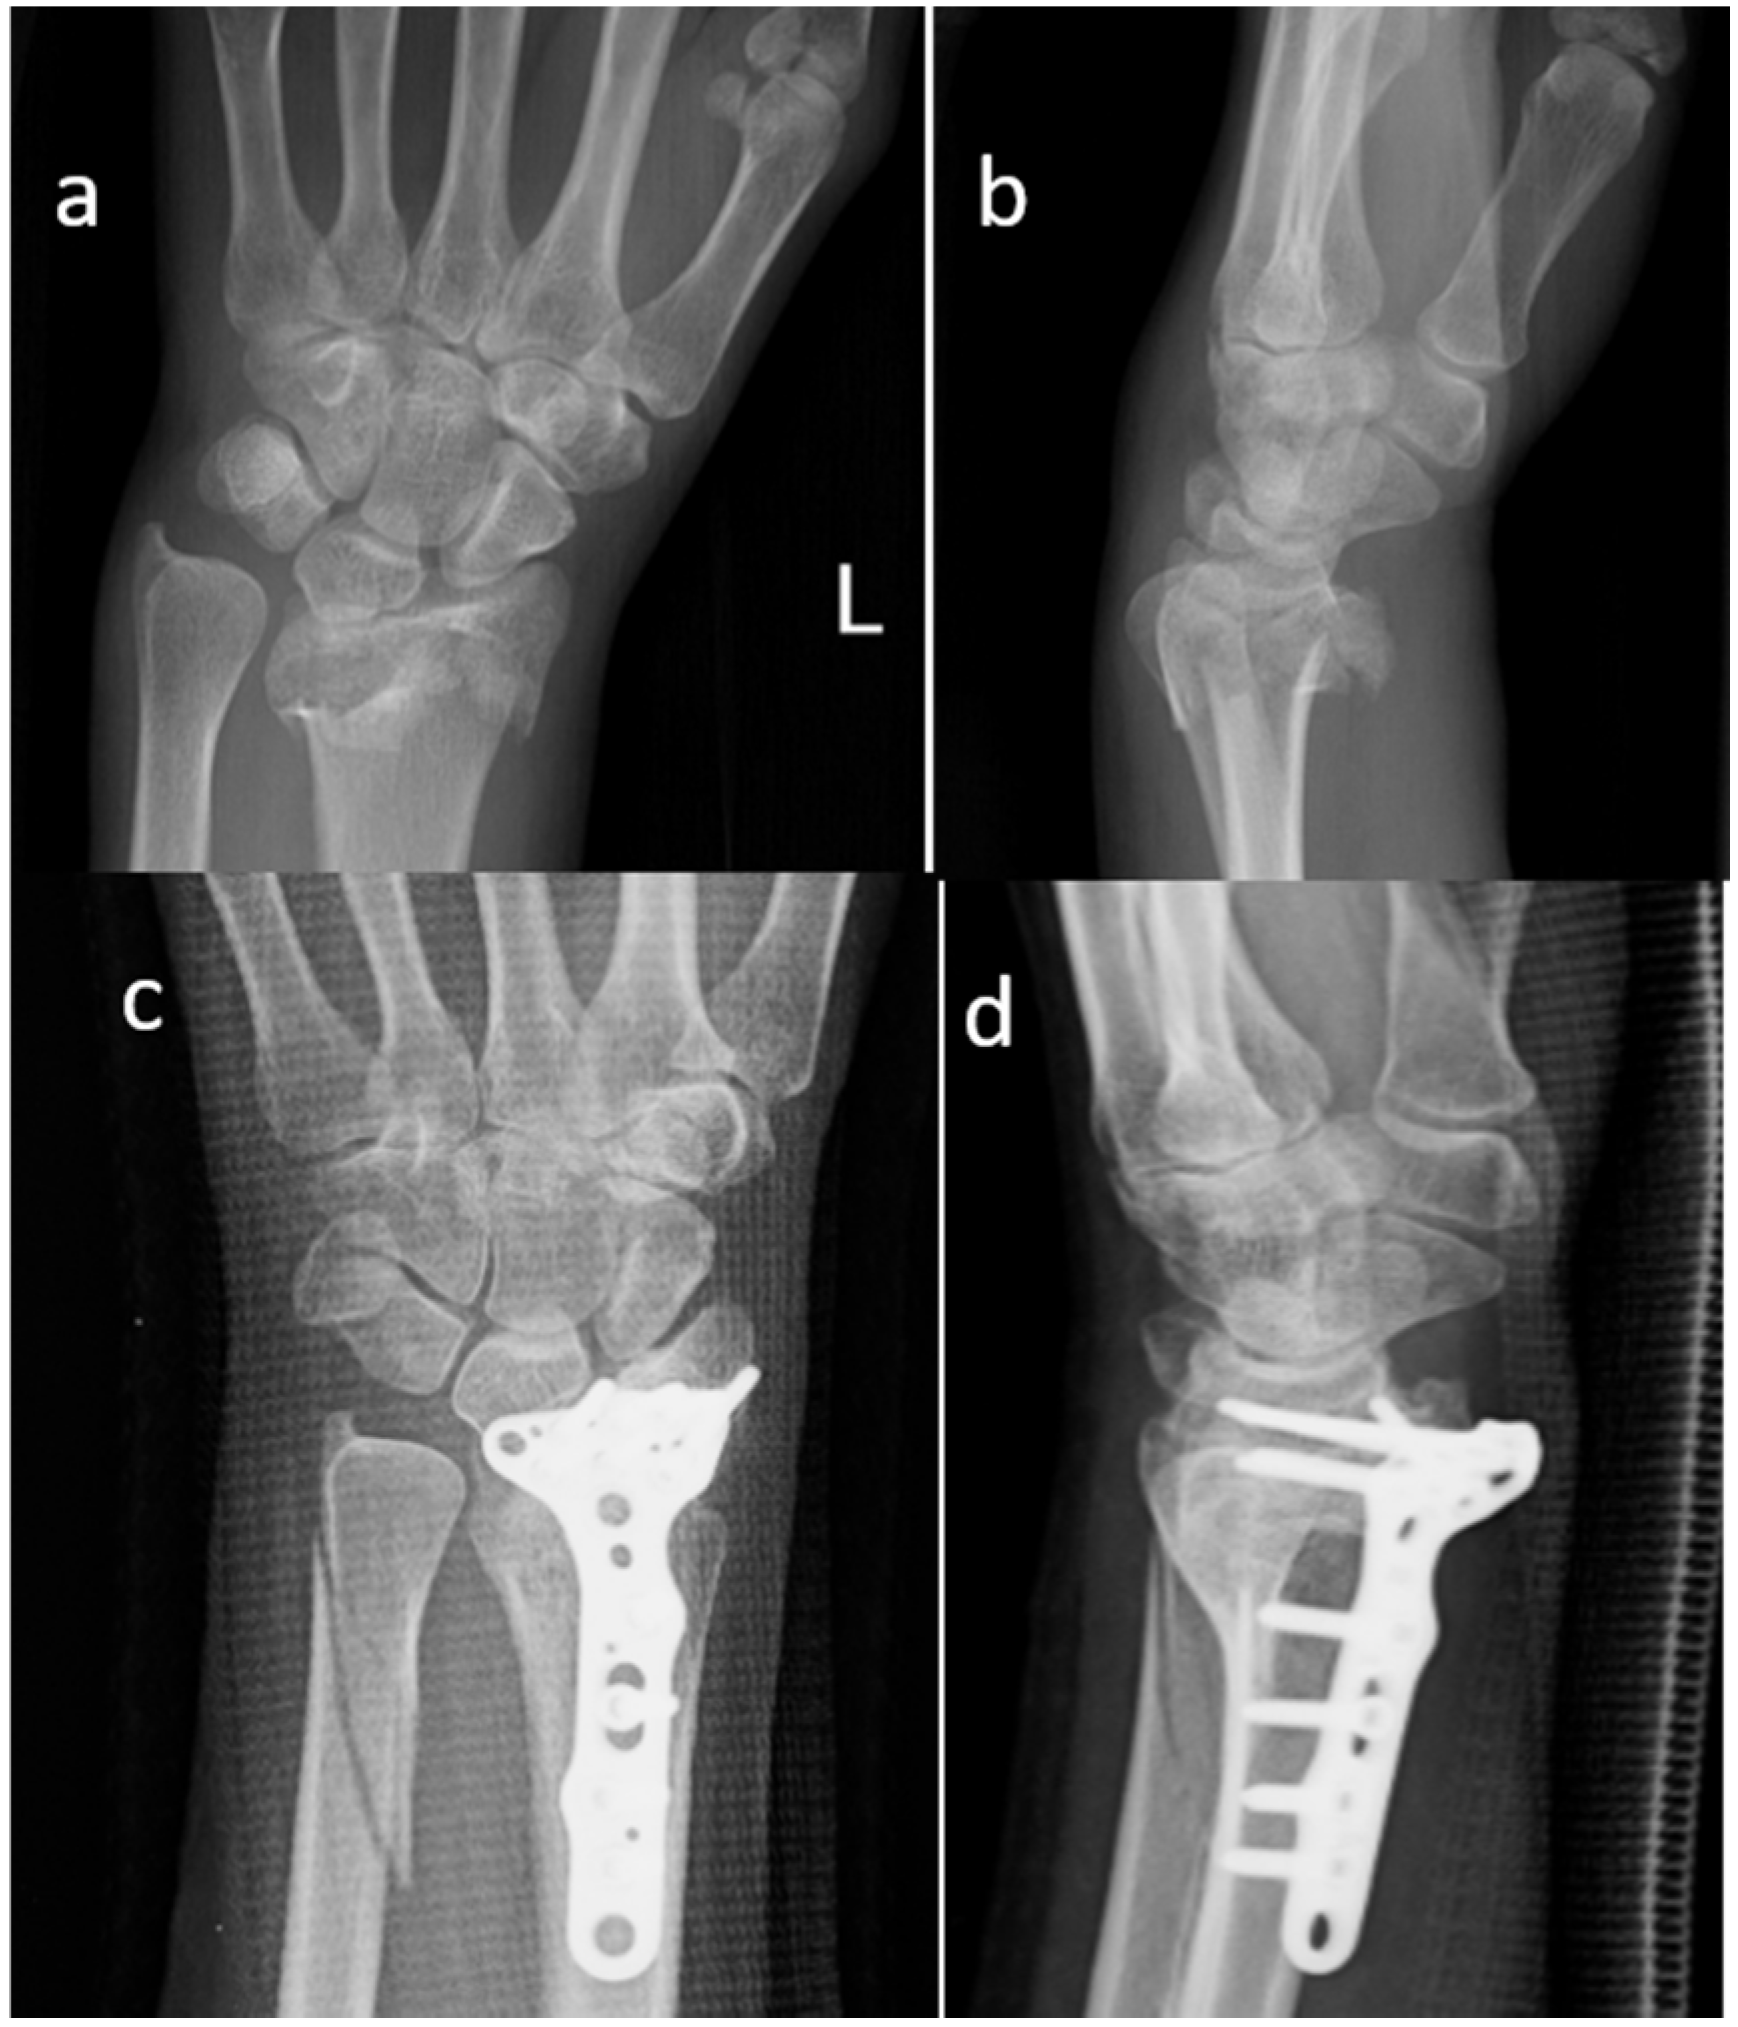

Figure 1.

Standard X-ray of a displaced articular fracture of the distal radius associated with multifragmented distal ulnar fracture. Preoperative images in AP (a) and Lateral (b) view are compared to post-operative X Ray at 2 months (c,d). The osteosynthesis appears stable and the xenograft block appears stable. (Female, 34 yy).

All the patients performed radiographic examinations during regular follow-up. Radiographs were examined for callus formation, bone resorption, implant stability, and SB integration [28] (Figure 1, Figure 2 and Figure 3).